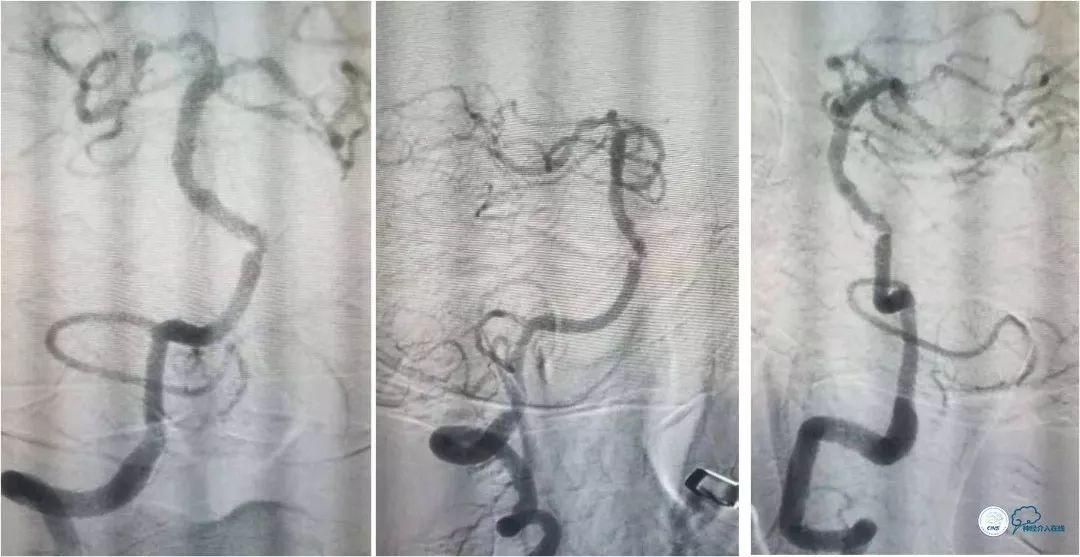

DSA提示:左椎动脉开口迂曲,右椎动脉开口中度狭窄(图5)。双椎动脉V4段与基底动脉交界处重度狭窄,左侧狭窄程度更重(图6,7)。

图5

图6

图7